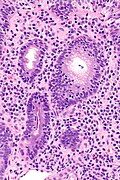

Lymphocytic gastritis. H&E stain. (WC/Nephron)

LM intraepithelial lymphocytes (>25 lymphocytes/100 epithelial cells)

Lymphocytic gastritis, abbreviated LG, is a rare form of gastritis, typically associated with celiac disease or Helicobacter pylori infection.

Features:[2]

• 25 lymphocytes / 100 epithelial cells.